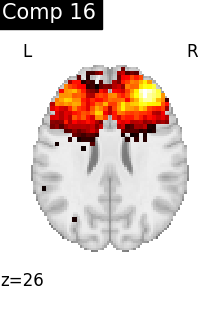

One plot of each component

for i, cur_img in enumerate(iter_img(dictlearning_components_img)):

plot_stat_map(

cur_img,

display_mode="z",

title=f"Comp {int(i)}",

cut_coords=1,

colorbar=False,

)

Compare CanICA to dictionary learning¶

Dictionary learning is a sparsity based decomposition method for extracting spatial maps. It extracts maps that are naturally sparse and usually cleaner than ICA. Here, we will compare networks built with CanICA to networks built with Dictionary learning.